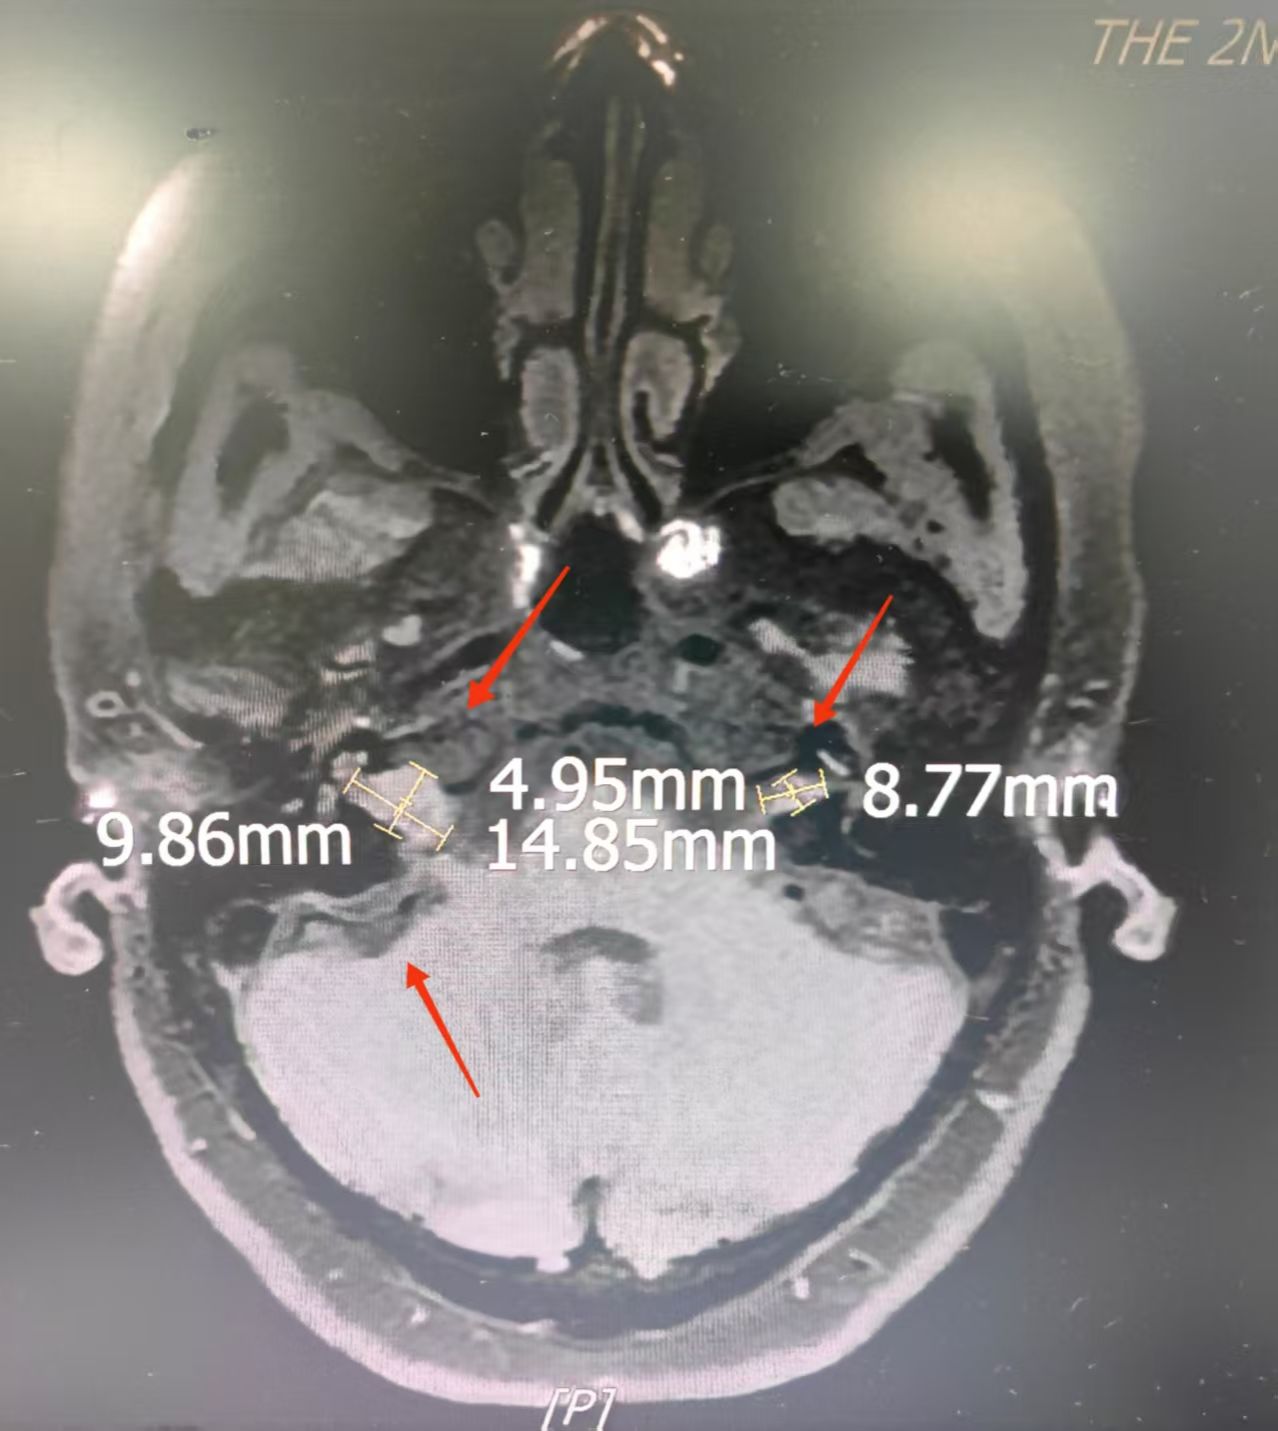

51岁的苑女士近两年来饱受双耳听力严重下降的困扰,辗转多家医院就诊均未见明显好转,其生活和心理因此受到严重影响。苑女士来到西安交通大学第二附属医院耳鼻咽喉头颈外科李阳副主任医师门诊就诊。李阳接诊后,经全面检查,发现苑女士双侧内听道存在团块状肿瘤,较大者位于右侧,考虑为听神经鞘瘤。同时,其右侧桥小脑区出现异常信号,提示脑膜瘤。听力检查结果提示:右耳极重度听力减退,左耳为重度听力减退,最终被确诊为2型神经纤维瘤病。